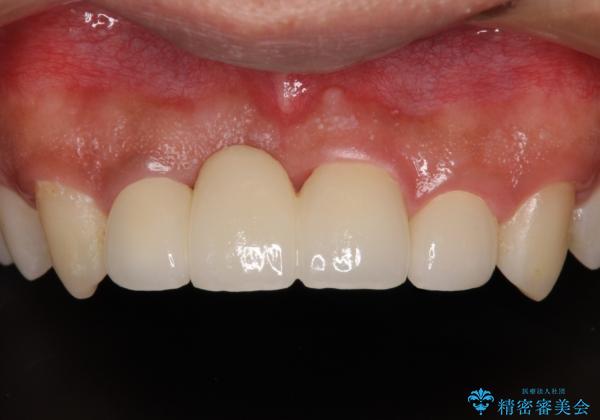

転んでぶつけて抜歯 前歯のオールセラミックブリッジ

- 酒席の後に転倒して前歯を損傷し、応急処置のみを受けてきたとのことで来院された患者様です。

損傷がひどく、前歯4本と広範囲であったため、症状やレントゲン写真、検査結果が一致せず、定期的に経過を見ながら診断していくこととしました。

右側前歯は歯根が短くなり、パンチング状に歯根に透過像が認められたため、予後不良と判断し抜歯することとしました。

当初のレントゲン写真では根尖部に骨透過像が認められた両サイドの2歯は、歯髄の正常な反応が認められたためそのまま保存し、左側前歯は歯髄が失活していたため根管治療を行うこととしました。

抜歯後の欠損部はブリッジにて補綴治療を行うこととしました。

事故直後のレントゲン写真では全ての歯の根尖部に骨透過像が認められましたが、治療後には全ての透過像がなくなっていました。

診断に2-3ヶ月かかりましたが、的確に診断を行うことができました。